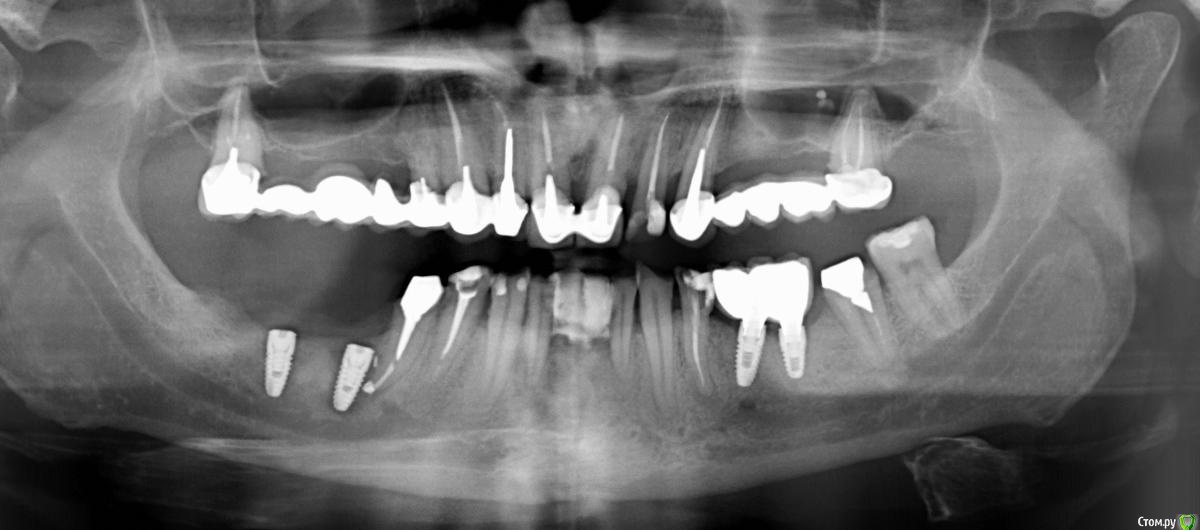

Колосс Опубликовано 25 марта, 2019 Автор Поделиться Опубликовано 25 марта, 2019 Имплант убралиДобрый день!Спасибо за советы и ответы.Имплант я убрал.Посмотрите пожалуйста нижнюю челюсть в комплексе.Мне разные специалисты рекомендуюта Больше никогда не имплантироваться.б. Оставить как есть.в. Перелечить или дернуть соседние зубы рядом с коронками на имплантах и укреплять импланты. Я не знаю что делать.От врача хочу отказаться.Он мне два раза импланты ставил на свищ и не обратил внимание на соседние больные зубы. У меня депрессия и полное непонимание, куда дальше двигаться.Есть КТ, но я не умею делать срезы. Снимок от 15.03.2019 1 Ссылка на комментарий